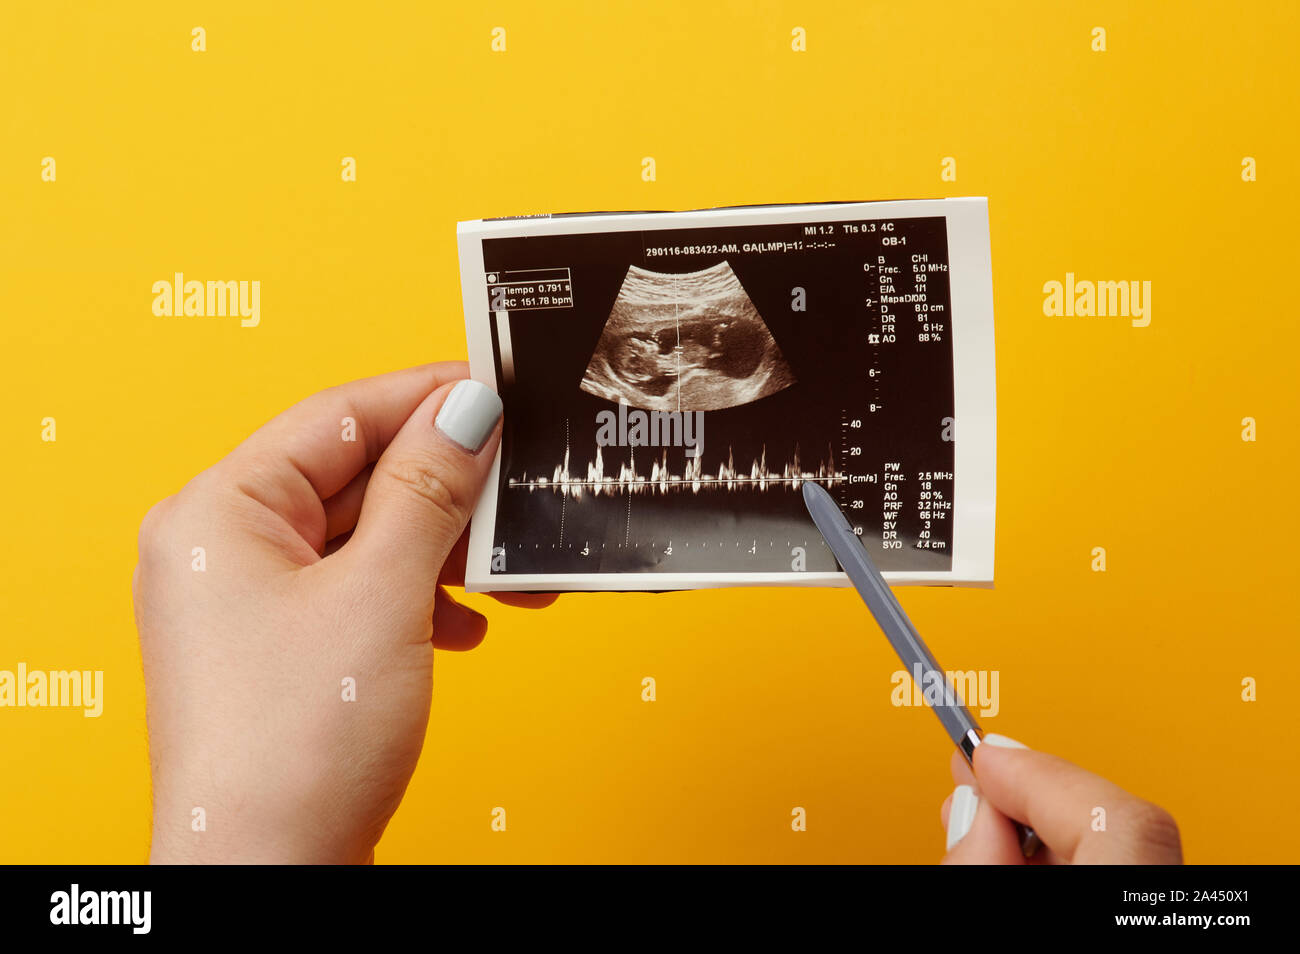

Il battito cardiaco del bambino nel ventre sulla foto di ultrasuoni Foto Stockhttps://www.alamy.it/image-license-details/?v=1https://www.alamy.it/il-battito-cardiaco-del-bambino-nel-ventre-sulla-foto-di-ultrasuoni-image329566105.html

Il battito cardiaco del bambino nel ventre sulla foto di ultrasuoni Foto Stockhttps://www.alamy.it/image-license-details/?v=1https://www.alamy.it/il-battito-cardiaco-del-bambino-nel-ventre-sulla-foto-di-ultrasuoni-image329566105.htmlRF2A450X1–Il battito cardiaco del bambino nel ventre sulla foto di ultrasuoni